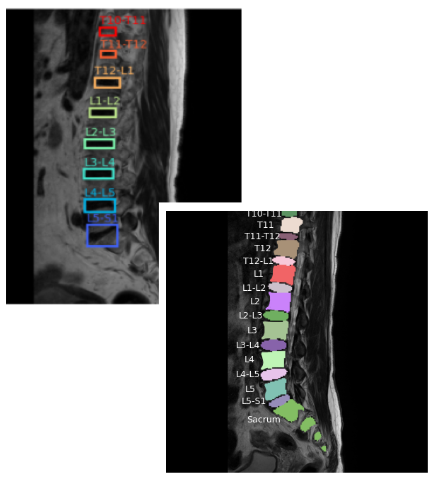

Spinal Segmentation Model Development Using U-Net and Disc Labeling

This project focuses on developing a spinal segmentation model using U-Net to accurately segment the vertebrae, discs, and sacrum.